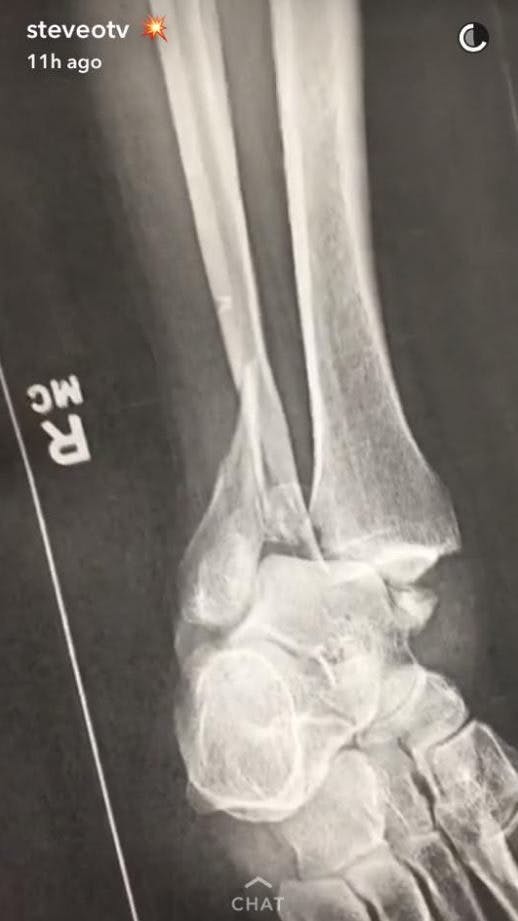

Steve-O har endnu ikke afsløret, hvordan han brækkede begge sine ben, men han fortæller, at det ene brud er sket i hælen, mens han har fået hele tre brud i sin anden ankel.

Også røntgen-billedet afslørede, at foden ikke havde det for godt. Foto: Snapchat